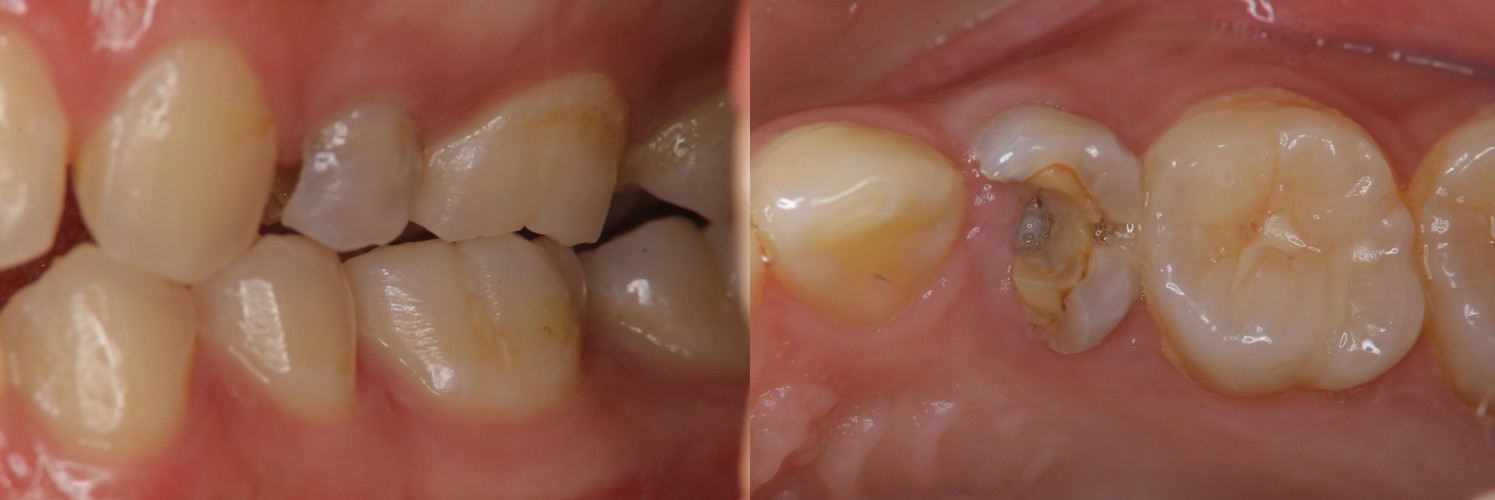

治療前,左上小臼齒區二次蛀牙

治療前,原根管治療已再污染